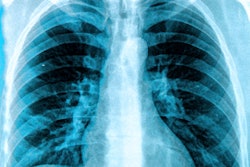

The researchers included TB screening exams from a previous study in incarcerated individuals at three male prisons in Brazil from October 2017 to December 2019. All individuals underwent portable chest x-ray exams, with sputum collected to confirm TB by lab tests. The images were evaluated individually using CAD4TB v6 (Delft Imaging Systems), Lunit Insight CXR2 v3.1 (Lunit), and qXR v3 (Qure.ai), with results compared for accuracy.

Among 2,075 incarcerated individuals, 259 (12.5%) had confirmed TB. In these individuals, all three algorithms performed similarly overall with areas under the receiver operating characteristic curve of 0.88 to 0.91, according to the findings.

At 90% sensitivity, only Insight CXR2 and qXR met WHO requirements for a triage test, with specificities of 84% and 74%. All algorithms had variable performance by age, prior TB, smoking, and presence of TB symptoms, with Insight CXR2 being the most robust to this heterogeneity, the researchers noted.